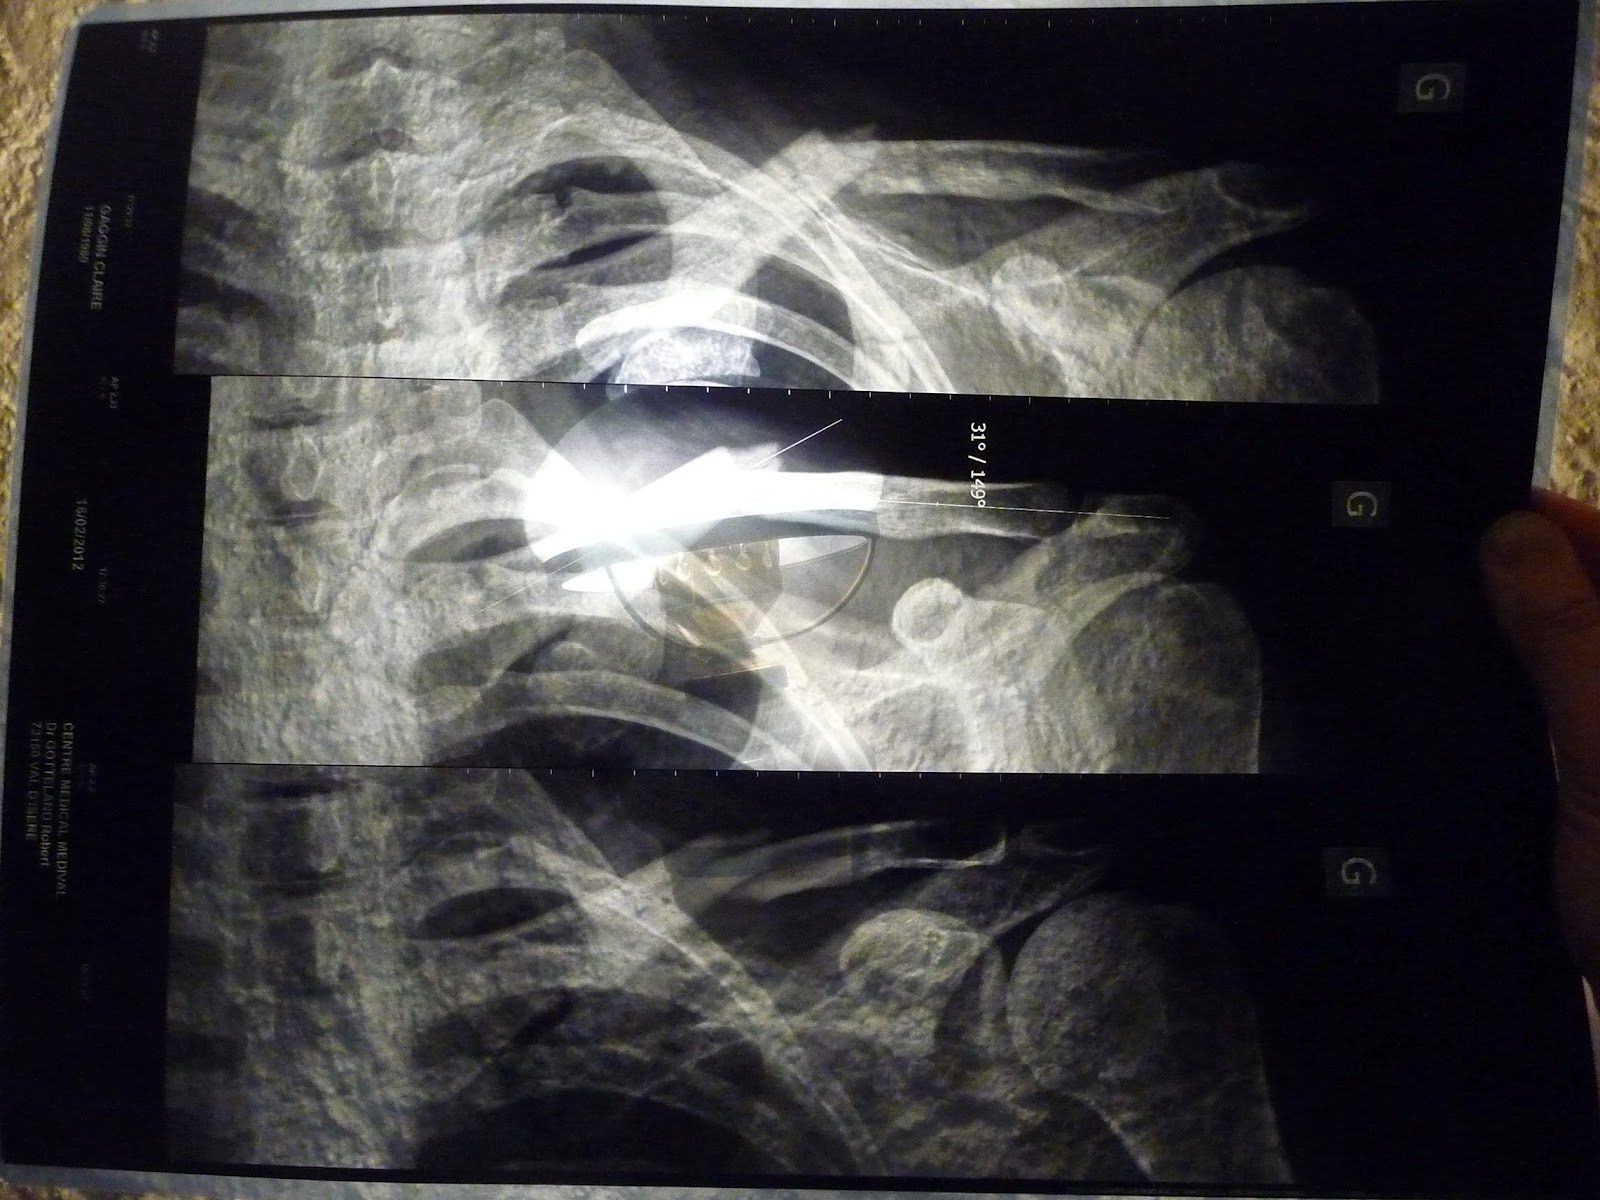

Straight away I could tell this fall was a bit worse as there was limited movement in my left arm and my shoulder was screaming. Luckily there was a bus back to Val d'Isere within half an hour, and Paul & Irene were there to help me down to Tignes Le Lac in time to catch it. As you can see, the xray shows my collar bone pretty well snapped (and it was protruding but at least not through the skin). Treatment is a fairly restrictive arm/shoulder brace that keeps my arms back and shoulders as straight as possible for 4 weeks while the bone heals...1 week & 4 days to go... I'd be lying if I said I wasn't counting ;-)

I think the top xray is first off then the bottom one is after they pushed the bone back down

(a drama in it's own right involving gas and an injection) |